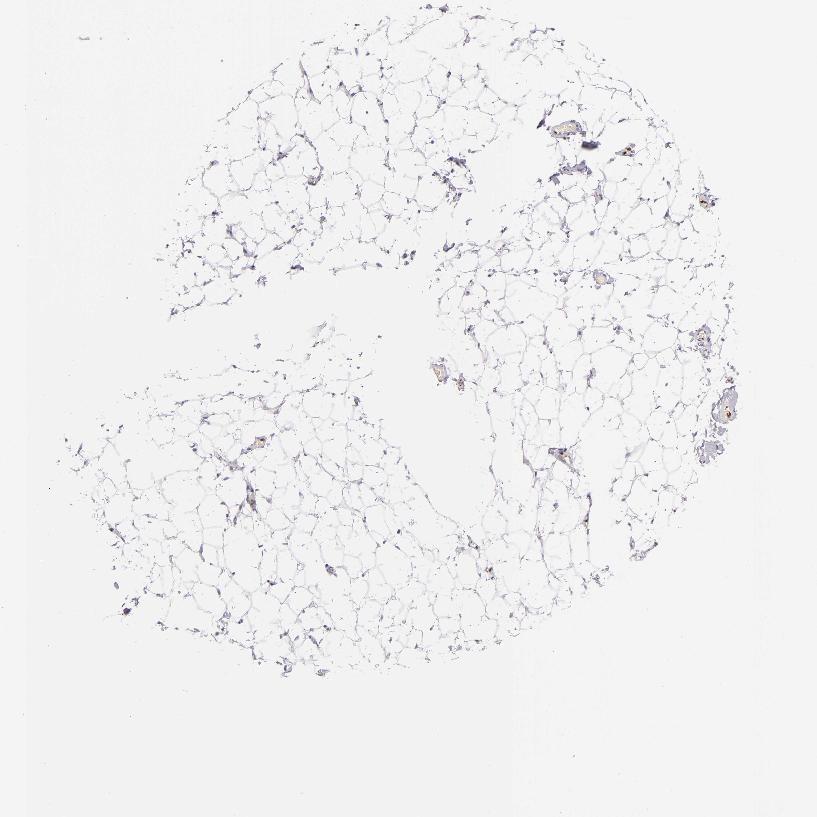

SOFT TISSUE 1 - Antibody stainingi

Antibody staining in the annotated cell types in the current human tissue is reported as not detected, low, medium, or high, based on conventional immunohistochemistry profiling in selected tissues. This score is based on the combination of the staining intensity and fraction of stained cells.

Each image is clickable and will lead to virtual microscopy that enables deeper exploration of all samples and also displays staining intensity scores, fraction scores and subcellular localization as well as patient and tissue information for each sample.

Antibody HPA013316Antibody CAB002496

Fibroblasts Not detectedNot detected

Peripheral nerve MediumNot detected